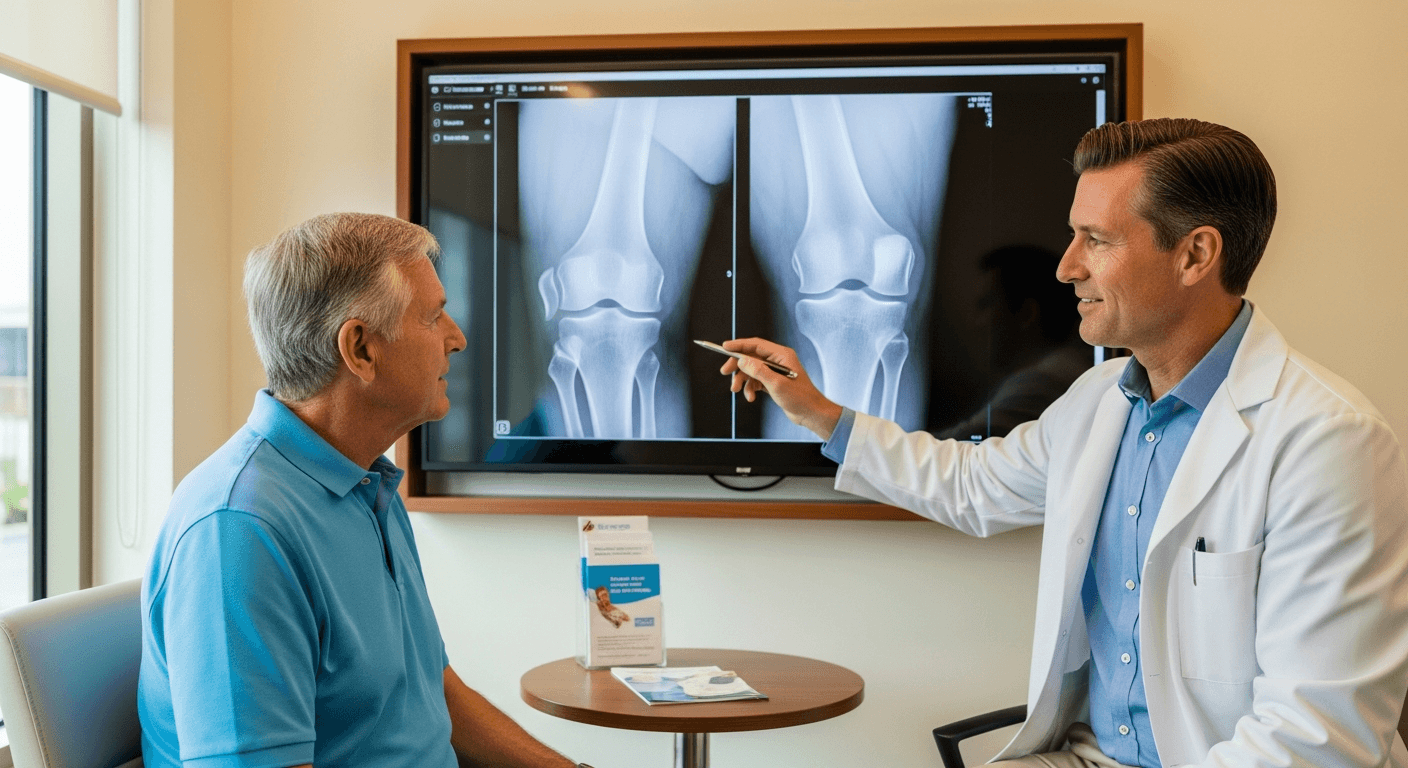

A specialist who sits down and explains your options

When you come to M&S for knee or shoulder pain, you meet a board-certified specialist who reviews your own imaging with you, explains what is causing the pain, and walks through every option. We look at minimally invasive, non-surgical approaches whenever they fit your case, so you understand the plan before anything moves forward.

Real time with your doctor

We review your imaging and explain the plan